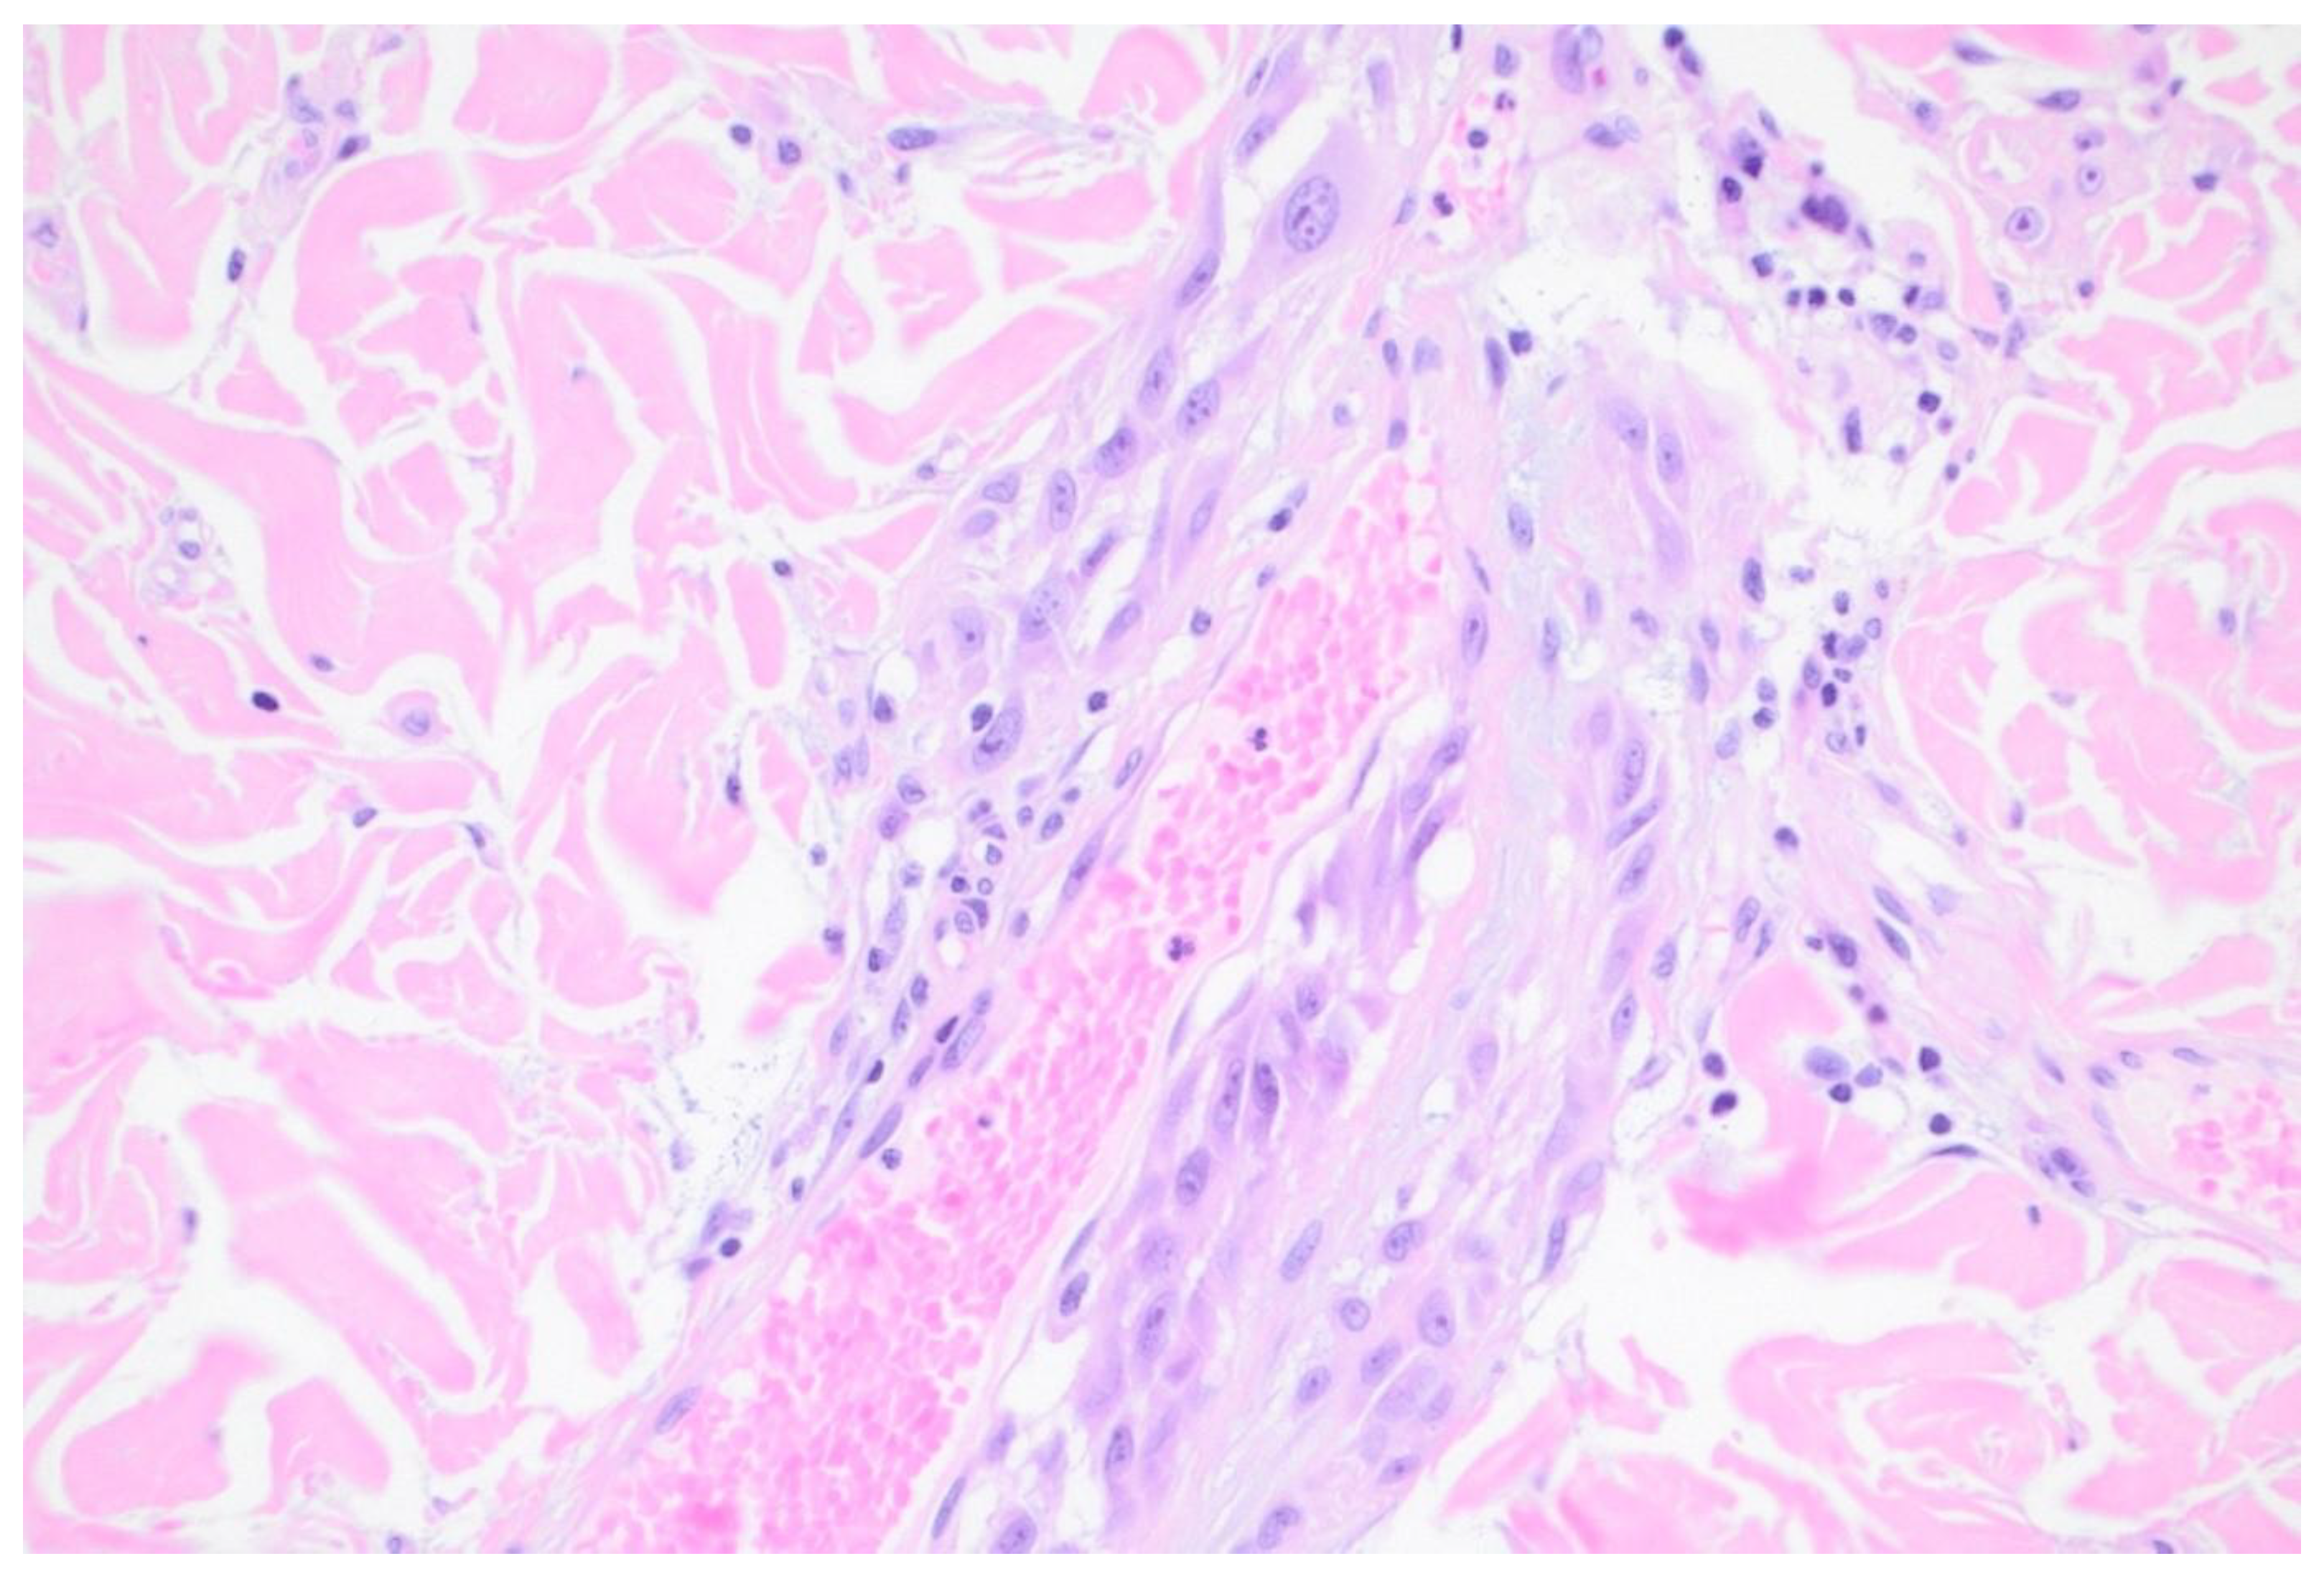

Extravascular migratory metastasis of melanoma (EVMM) is the spread of melanoma cells on the external surfaces of vessels. This involves pericyte mimicry by melanoma cells. Pericytes are multifunctional, modified smooth muscle cells present in capillaries. EVMM is associated with regional and distant metastases in primary cutaneous melanomas. This phenomenon is probably under reported.[39] [Figure 2]

Figure 2. Extravascular migratory metastasis of melanoma. H&E x600.